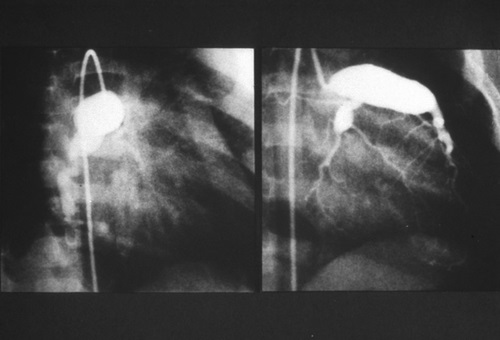

Aneurisma gigante de arterias coronarias

La complicación más grave son los aneurismas de la arteria coronaria. Las arterias coronarias son los vasos sanguíneos que transportan sangre oxigenada al músculo del corazón. Un aneurisma es una dilatación de un sector de un vaso sanguíneo. Cuando una arteria se dilata (más de lo normal), la sangre circula más despacio porque se encuentra a un presión más baja. El cambio de presión y de velocidad facilita la formación de coágulos, lo que puede provocar infartos. Con el tiempo, los aneurismas de la arteria coronaria se pueden curar.